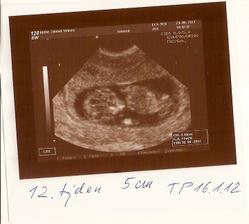

10.8.11 utz u MUDr.Vebery, vsechno v poradku, Emicka ma cca 15cm a 170g. Potvrzena holcicka;)